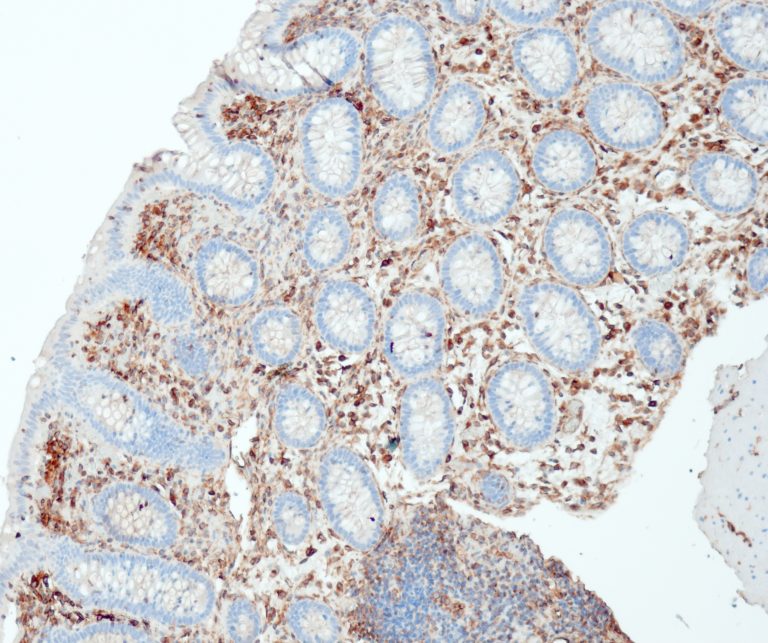

Gastrointestinal (GI) Pathology